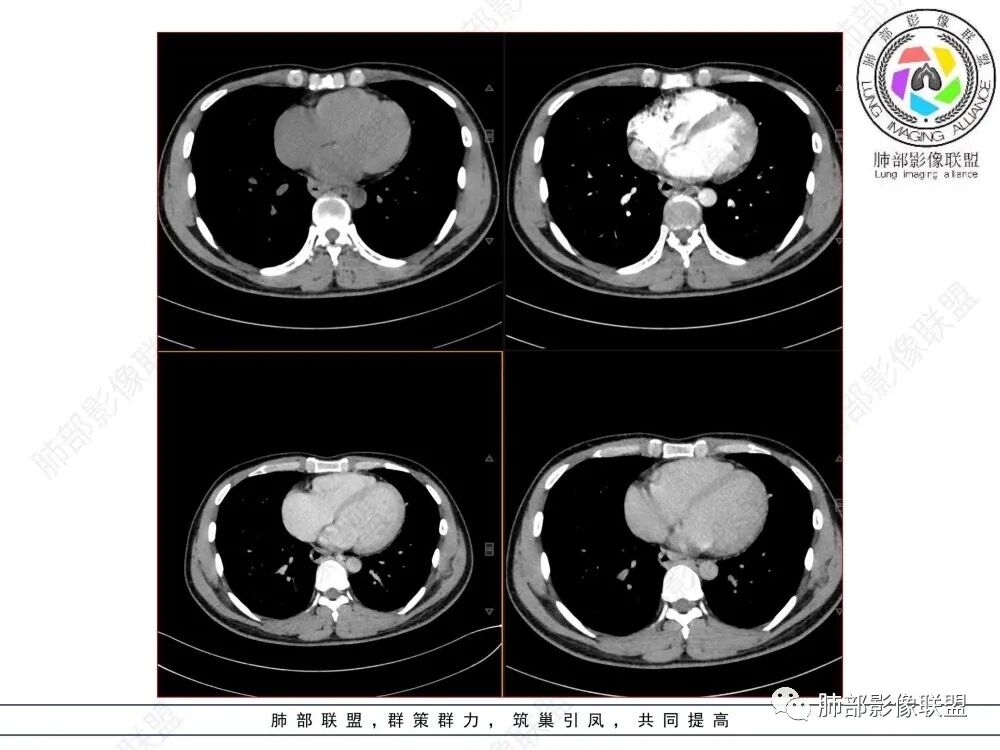

影像学特点:类纵隔区病变,沿食管生长,形态不规则,但边界清楚,内部信号/密度均匀,强化程度比较弱。

影像诊断思路:起源食管肿瘤(非黏膜起源,肌层起源),良性或低度恶性肿瘤可能性大,一般以神经鞘瘤、胃肠间质瘤及平滑肌瘤为主。食管神经鞘瘤强化明显均匀、以食管上段多见,周围常见炎性增大淋巴结,不太符合;胃肠间质瘤小的比较均匀,大的不均匀,但强化程度较高;影像上看这例病例比较符合平滑肌瘤。

食管平滑肌瘤是最常见的食管良性肿瘤,多见于男性,男女之比为2.6:1,高发年龄 30~60岁之间与食管癌相比,食管平滑肌瘤 的一个主要特点是病史相对较长,病情进展缓慢。病史最长者达10年余,平均 15.7个月,尽管病史较长,但大多数患者仍能进普食。食管平滑肌瘤的诊断一般比较容易,结合患者临床症状、食管造影及食管镜所见,一般均能得出正确诊断。食管造影主要为充盈缺损,病变与食管壁成锐角,粘膜线连续无破坏,管腔收缩扩张比较自如。钡餐造影敏感性高,但对食管壁间及食管周围情况难以判断。CT具有极高的密度分辨率,并且可以获得高质量的多平面重组图像,有利于食管壁间及食管周围情况的判断,表现为食管下段环绕管壁生长,偏心性或薄厚不均软组织密度肿块,密度均匀,内缘分叶状,管腔与正常食管壁构成不规则多角形扩张,增强动脉期无强化,多角度重建其病灶长轴与食管长轴不一致。由于食管壁在收缩状态下厚度约为5.6mm,扩张状态厚度不超过3mm,CT扫描时保持食管处于扩张状态可提高小病灶检出率。MR表现为T1加权等信号,T2加权稍高信号,可见高信号粘膜层,增强扫描轻度渐进性强化,密度均匀,无出血坏死。对于粘膜及周围脂肪间隙的判断具有明显优势。